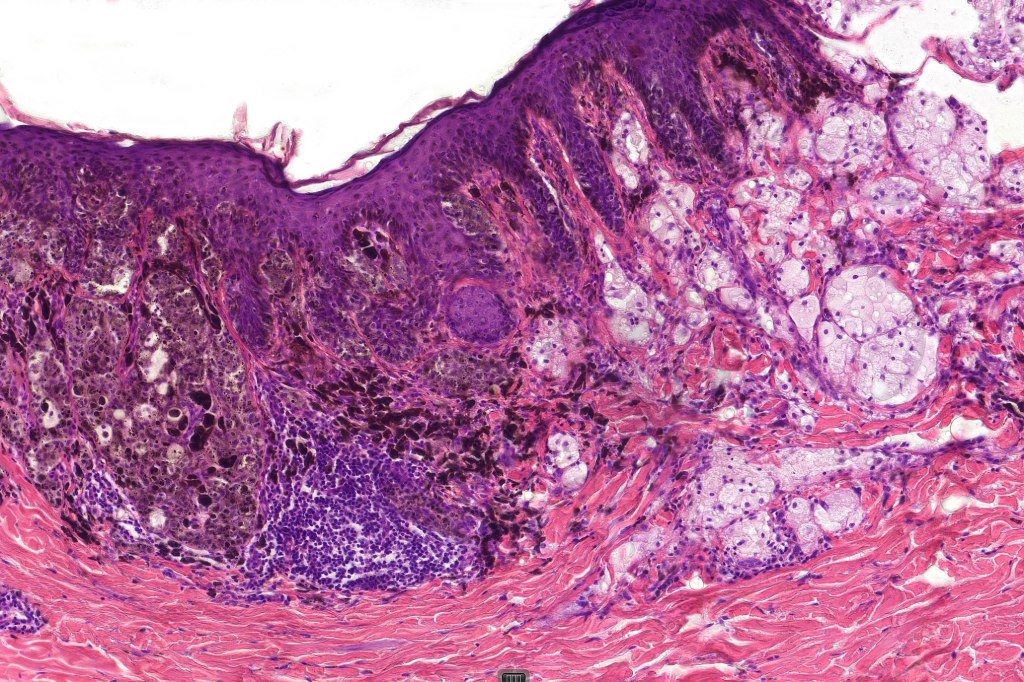

Histological features

•May affect the tumor in part or whole

•Enlarged cells with copious eosinophilic, foamy or clear cytoplasm (some authors include melanoma with clear cell change in the same category)

•Variable pigmentation

•Nuclei vesicular or hyperchromatic

•Pleomorphism is not generally marked and indeed can be very subtle

•Variable mitotic activity